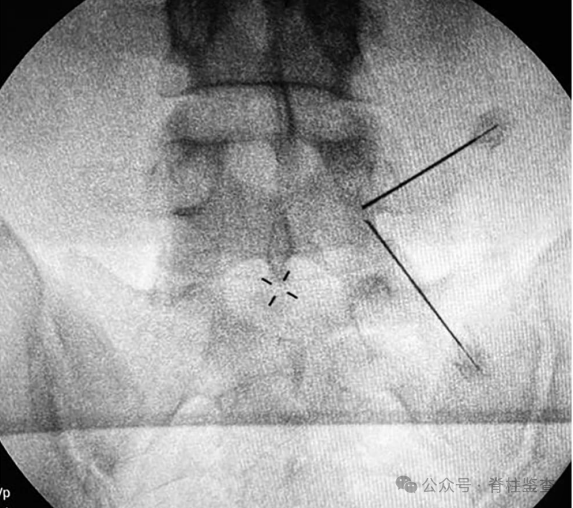

透视正位标记椎间盘上下界限和上下椎弓根。

目标点为椎板峡部,可预先在皮肤表面标记。

第一个手术切口与横突相对应,第二个切口在第一个切口的尾侧约3cm处,椎弓根线外缘2-3cm处切开水平切口。